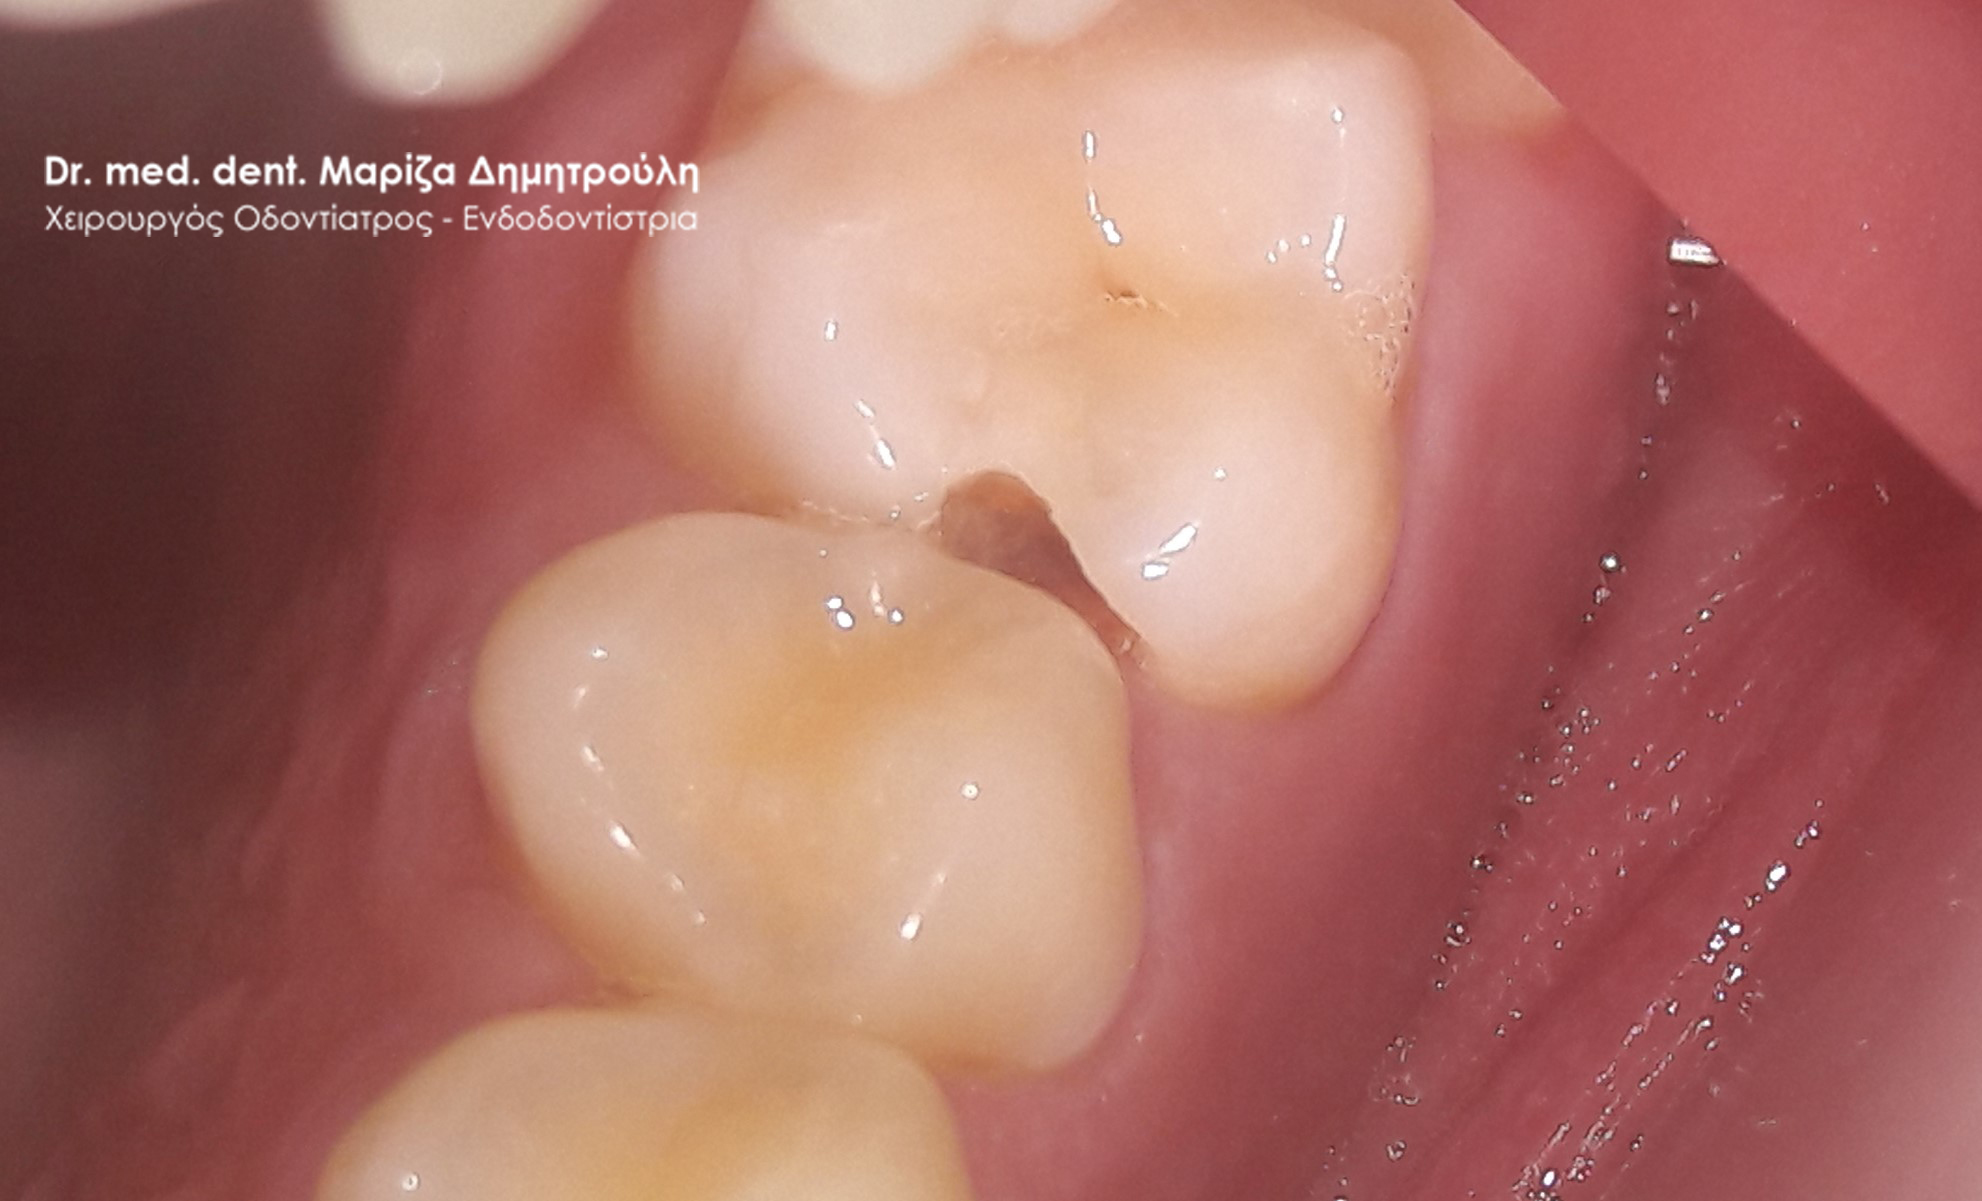

Η ασθενής προσήλθε με έντονο πόνο στο ιατρείο και είχε λάβει τις προηγούμενες μέρες αντιβίωση, εφόσον στην άνω αριστερή πλευρά της είχε οίδημα. Μετά την κλινική εξέταση διαπιστώθηκε η ύπαρξη ενός συριγγίου υπερώια μεταξύ των δύο άνω αριστερών γομφίων. Πραγματοποιήθηκε ακτινογραφία με την τοποθέτηση ενός κώνου γουταπέρκας για τη διάγνωση του υπαίτιου δοντιού, που είχε προκαλέσει την εμφάνιση του συριγγίου. Σύμφωνα με όσα αποκάλυψαν η κλινική και ακτινογραφική εξέταση ακολούθησε η έναρξη απονεύρωσης στο δεύτερο άνω αριστερό γομφίο, δεδομένου οτι είχε ένα βαθύ λευκό σφράγισμα ρητίνης που εκτεινόταν στο ύψος του νεύρου του δοντιού. Το δόντι είχε έντονα συμπτώματα πόνου κατά την επίκρουσή του.

Μετά την ολοκλήρωση της απονεύρωσης στο δεύτερο άνω αριστερό γομφίο το δόντι είναι ασυμπτωματικό. Η αποκατάσταση του δοντιού πραγματοποιήθηκε με λευκό σφράγισμα ρητίνης, εφόσον το έλλειμμα των οδοντικών ιστών ήταν μικρό και δε χρειαζόταν η προστασία του δοντιού με θήκη / στεφάνη δοντιού.

Σε δεύτερη φάση θα ακολουθήσει η επανάληψη απονεύρωσης στον πρώτο άνω αριστερό γομφίο, καθώς η απονεύρωση του δεν καλύπτει όλο το μήκος των ριζών του δοντιού και το δόντι μετά το πέρας της ενδοδοντικής θεραπείας συνεχίζει να πονά.

ΠΡΙΝ

Εικόνα του δοντιού μετά τη διάνοιξή του και την επεξεργασία των ριζικών σωλήνων του δοντιού

Κλινική εικόνα του δοντιού με το υλικό έμφραξης στους ριζικούς σωλήνες του

Αποκατάσταση του δοντιού με λευκό σφράγισμα ρητίνης